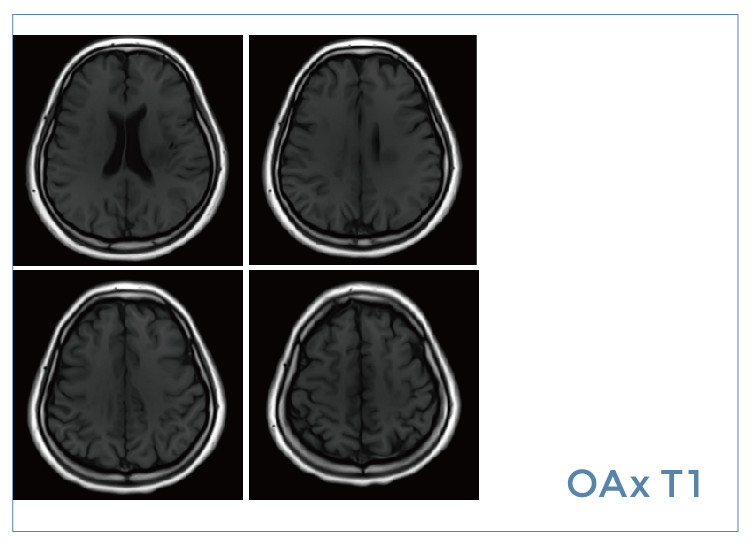

【朗润影像档案】20190823磁共振影像病例结果讨论